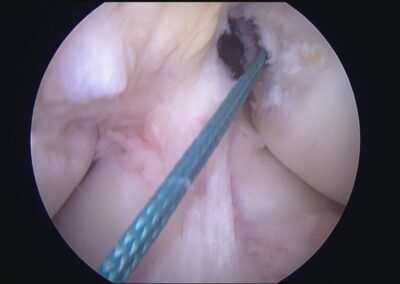

GalleryShoulder rotator cuff repair Meniscus root repair Meniscus repair Bankart repair for recurrent shoulder dislocation ACL reconstruction Machines Instruments